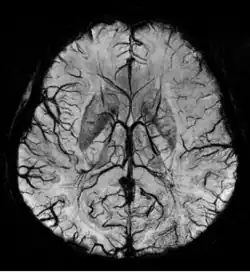

Im Gegensatz zur meist angestrebten signalreichen Darstellung der Gefäße gibt es auch die Möglichkeit, die Gefäße signalarm (dunkel) im umliegenden helleren Gewebe darzustellen. Dies wird beispielsweise für die Darstellung von Venen (MR-Phlebographie) mit T2*- und suszeptibilitätsgewichteten Pulssequenzen eingesetzt.

Zur Beurteilung und Diagnosefindung müssen die dreidimensional aufgenommenen Datensätze als zweidimensionale Bilder (am Bildschirm) dargestellt werden. Dafür gibt es verschiedene Nachverarbeitungstechniken: Die Daten können schichtweise entsprechend der ursprünglichen Aufnahmeorientierung betrachtet werden, sie können in beliebigen Ebenen (etwa rechtwinklig zum Gefäß oder mit dem Gefäß in der Bildebene) als multiplanare Rekonstruktionen (MPR) rekonstruiert werden, es können Maximumintensitätsprojektionen (MIP, maximum intensity projection) aus verschiedenen Blickwinkeln berechnet werden oder die Daten können als virtuelle dreidimensionale Objekte im Raum dargestellt werden.

Für alle fortgeschrittenen Darstellungstechniken ist eine Aufnahme möglichst isotroper Daten von Vorteil, bei denen also die Ortsauflösung in alle drei Raumrichtungen etwa gleich ist. Typische Ortsauflösungen liegen mit modernen Techniken (abhängig von der Größe der interessierenden Gefäße und des Aufnahmevolumens) zwischen 1,5×1,5×1,5 mm³ und 0,5×0,5×0,5 mm³.